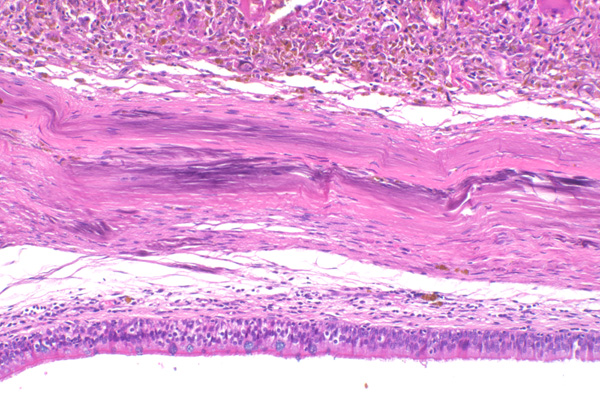

10x   |   Hematoxylin and Eosin

Mineralization of the submucosal connective tissue, and subepithelial edema.